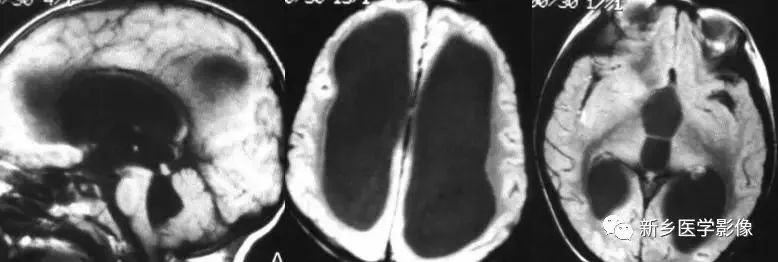

❽ 胼胝体发育不良

胼胝体发育不良可单独发病,但更常见的是伴有中枢伸经系统的其他畸形,包括胼胝体周围脂肪瘤、脑膨出、交通性脑积水、Chaiar-II畸形、Dandy-Walker囊肿、脑裂畸形等。

临床上可无症状或仅有轻度临床症状,临床检查可见眼距过宽、大头畸形、智力发育迟滞等。

胼胝体缺失时,MR冠状位上侧脑室前角呈新月形表现,侧脑室体部分离,呈垂直状平行走行。